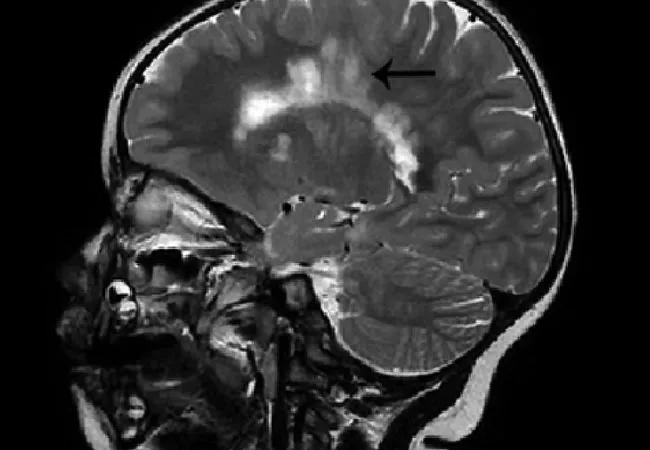

Figure. Brain MRIs in the case patient with arrows demonstrating extensive demyelination around the periventricular and deep white matter areas (left) and demyelinating plaques arranged perpendicular to the corpus callosum in a typical “Dawson fingers” pattern (right). Reprinted from Sivaraman and Moodley (Neurodegen Dis Manag. 2016;6:31-36) with permission of Future Medicine Ltd.

At the most recent clinical encounter, 33 months after initial presentation, the child remained clinically asymptomatic, but repeat brain MRI showed extensive white matter lesions — some new — involving the periventricular, pericallosal and subcortical areas.